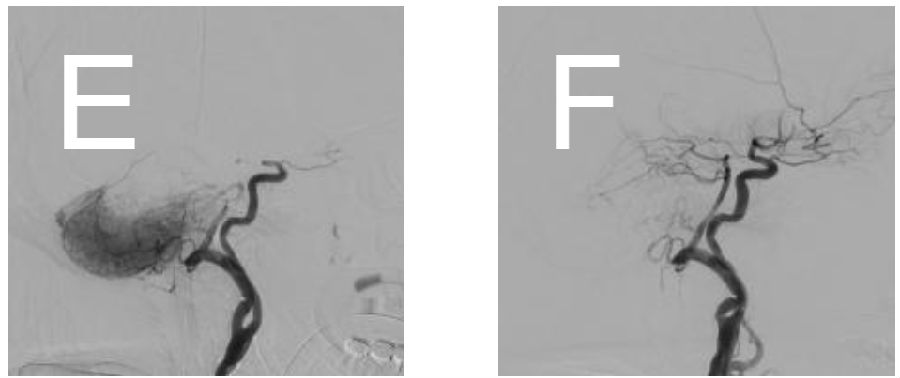

机械血栓切除术后基底动脉再通前(E)后(F)的血管造影图像。